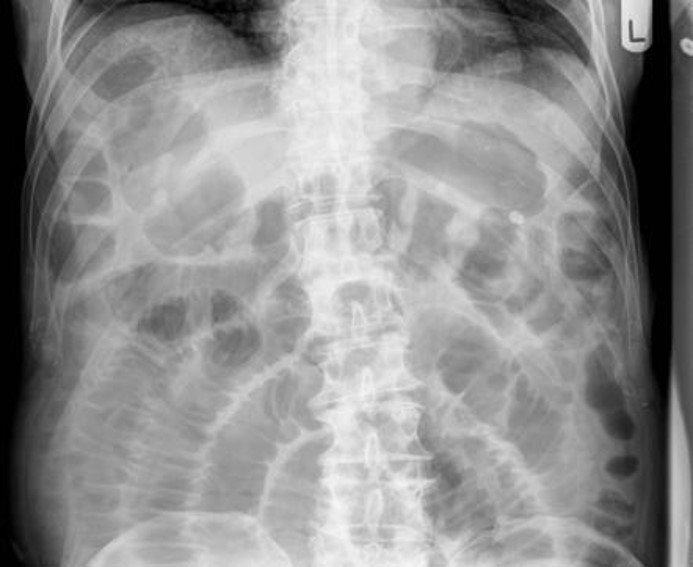

What is shown in the AXR?

Sigmoid volvulus